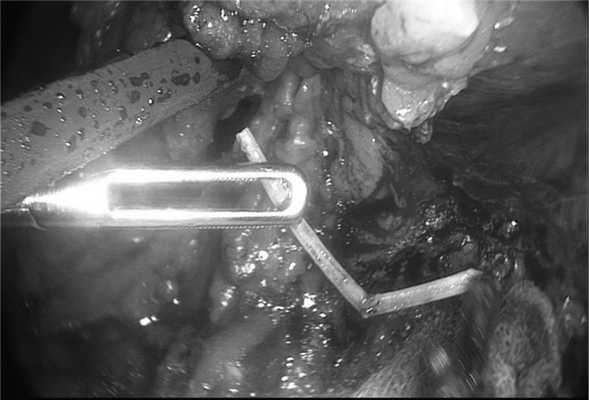

Через 14 дней выполнена операция: видеолапароскопия, адгезиолизис, удаление инородного тела из брюшной полости, ушивание стенки желудка. При этом в верхнем этаже брюшной полости отмечен выраженный спаечный процесс с формированием воспалительного инфильтрата, распространяющегося на желудок, левую долю печени и большой сальник (рис. 6).

При разделении инфильтрата выявлено инородное тело (рыбная кость, рис. 7, 8), исходящее из стенки желудка. Выполнено удаление инородного тела с последующим ушиванием дефекта серозно-мышечного слоя желудка отдельными узловыми швами.

Рис. 7. Пациент П. Видеолапароскопия. Инородное тело желудка (кость) .